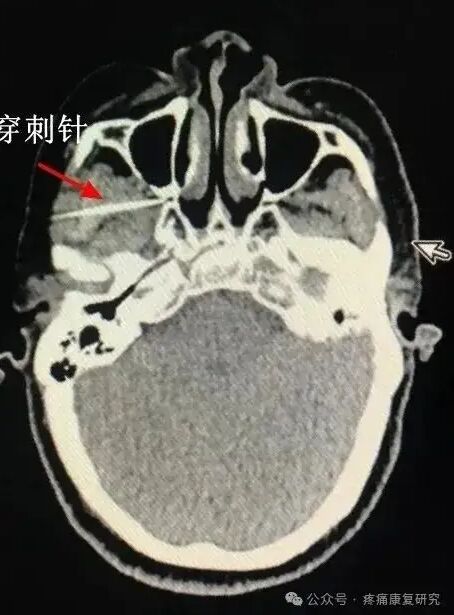

针具到位:

蝶腭神经节针刺

治疗过敏性鼻炎